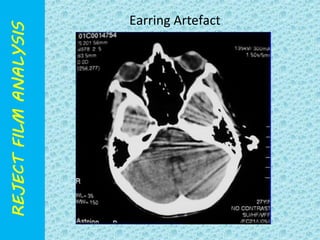

• JEWELLERY

Earring Artefact